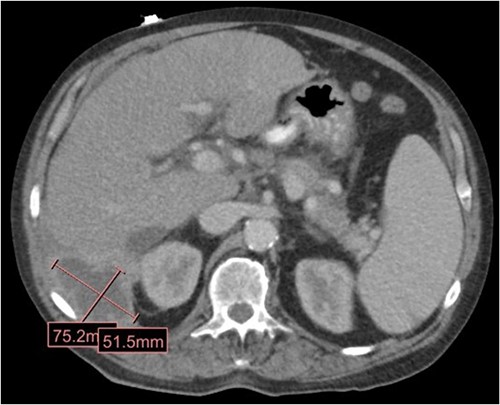

The patient is a 63-year-old male who underwent laparoscopic cholecystectomy with intraoperative cholangiogram for symptomatic gallstone disease at an outside hospital 2 years prior to our initial visit. His postoperative course was complicated by biloma and retained gallstones in the common bile duct, for which he underwent endoscopic biliary sphincterotomy 4 months after the initial surgery. His medical history was notable for alcoholic cirrhosis with a Model for End-Stage Liver Disease score of 14, duodenal ulcers, and gastric angiodysplasia. Symptoms included intermittent abdominal discomfort, nausea, and vomiting 1 year after the cholecystectomy. Computed tomography (CT) showed a perihepatic abscess measuring up to 7.5 × 5.1 cm, containing gallstones and punctate free-air near the right hepatic lobe (Fig. 1). He underwent image-guided percutaneous drainage of the hepatic abscess. A fistulogram via the abdominal drain demonstrated communication between the abscess cavity and the second segment of the duodenum, confirming the presence of a duodenal-perihepatic fistula, feeding the abscess cavity (Fig. 2). Interestingly, the oral contrast administered during a prior abdominal CT scan did not demonstrate this fistulous connection. The patient underwent endoscopic closure of the fistula using an over-the-scope clip device (Fig. 3). Repeat CT 2 months following the closure showed that the perihepatic abscess decreased in size with no evidence of a new abscess. On initial follow-up, the patient demonstrated clinical improvement in his overall health. Continued follow up revealed near complete resolution of the perihepatic abscesses and continued clinical improvement.

CT in the transverse plane demonstrating a perihepatic gallstone-containing collection of fluid measuring up to 7.5 × 5.1 cm.